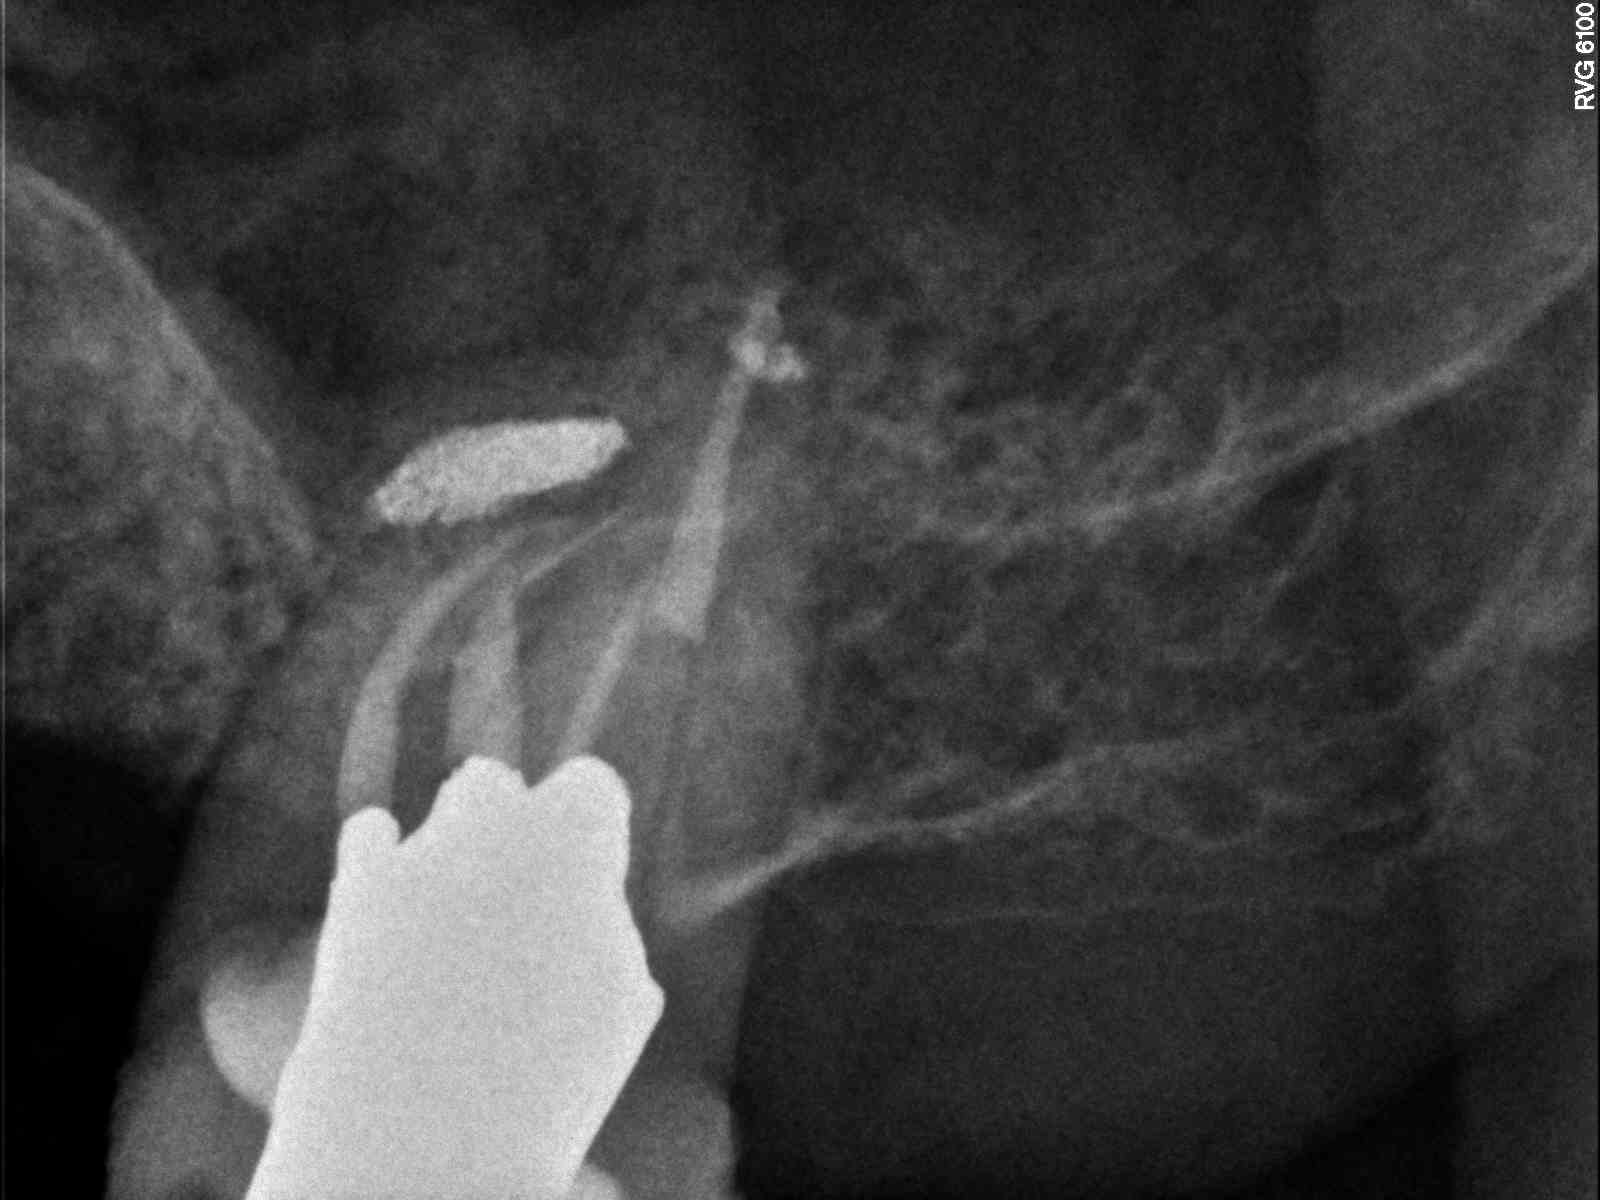

| CaOH. 2mm piece SX at length MB2 |

![]() |

| Risk outweighs any benefit of retrieval at this point. Piezo attempt for awhile but too far around last curve to even visualize at this point so quit |